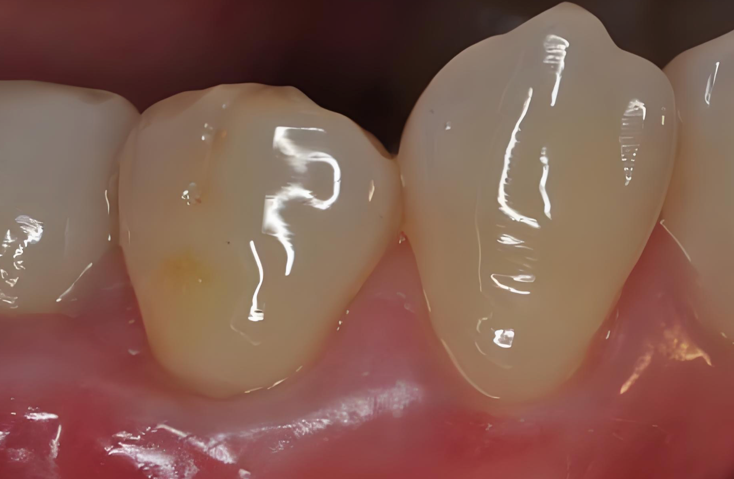

这个区域的菌斑堆积,会同时引发两大问题:一是牙颈部蛀牙(颈部龋),这个位置的牙体组织本身较薄,一旦发生蛀牙,很容易累及牙神经;二是牙周炎,菌斑中的毒素会持续刺激牙龈,引发红肿、出血,进而导致牙槽骨吸收、牙龈退缩、牙齿松动。

图4:牙齿和牙龈交界的位置也是刷牙的重点。